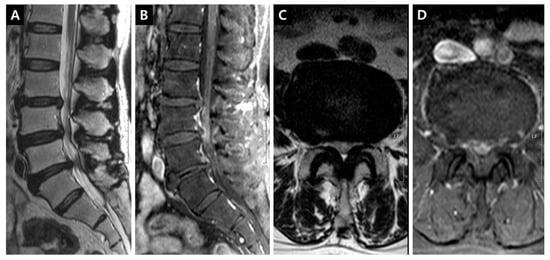

Figure 4. Enhancement patterns: intraradicular vein of cauda equina (IRCE). (A) T2-weighted midsagittal image showing L3-4 central protrusion, L4-5 central stenosis, and L5-6 central protrusion; (B) Fat-suppressed enhanced T1-weighted midsagittal image revealing the prominent enhancement of intradural rootlets on the L4-5 disc level; (C) T2-weighted axial image on the L4-5 disc level; (D) Fat-suppressed enhanced T1-weighted axial image on the L4-5 disc level, the definite enhancement of rootlets in the thecal sac can be seen.

DCSAs were measured on the T2-weighted axial plane at the most stenotic level in all stenosis groups and at the L3–4 and L4–5 levels in the control group. The presence of enhancement patterns such as PVCE, DVCE, and IRCE was assessed qualitatively at the level of stenosis. PVCE indicated the enhancement of the periradicular vein and was regarded as a part of the longitudinal vein in anterior IVVP or PEVC (Figure 2). DVCE designated the enhancement of the dorsal epidural venous plexus in the posterior IVVP (Figure 3). IRCE indicated the enhancement of the intraradicular vein within intrathecal rootlets (Figure 4). The author assumed that these enhancement patterns (PVCE, DVCE, IRCE) developed according to the degree of venous congestion and reflux.